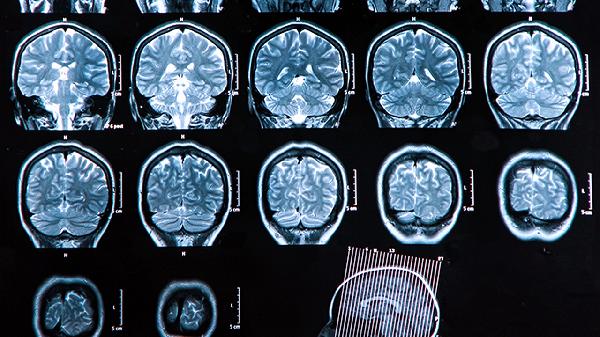

脑血栓患者去世前可能出现意识障碍、呼吸异常、瞳孔变化、血压骤降、四肢冰冷等征兆。这些表现通常与脑干功能衰竭或多器官功能衰竭有关,需立即采取医疗干预。

意识障碍是脑血栓终末期的常见表现,患者可能从嗜睡逐渐发展为昏迷,对外界刺激无反应。部分患者会出现谵妄或烦躁不安,可能与脑缺氧或颅内压增高有关。呼吸异常表现为呼吸频率不规则,如潮式呼吸或长吸气呼吸,提示延髓呼吸中枢受损。瞳孔变化包括双侧瞳孔散大固定或不等大,反映脑干受压或疝形成。血压骤降通常伴随心率减慢,显示心血管调节中枢功能丧失。四肢冰冷伴皮肤花斑样改变,是外周循环衰竭的典型表现。